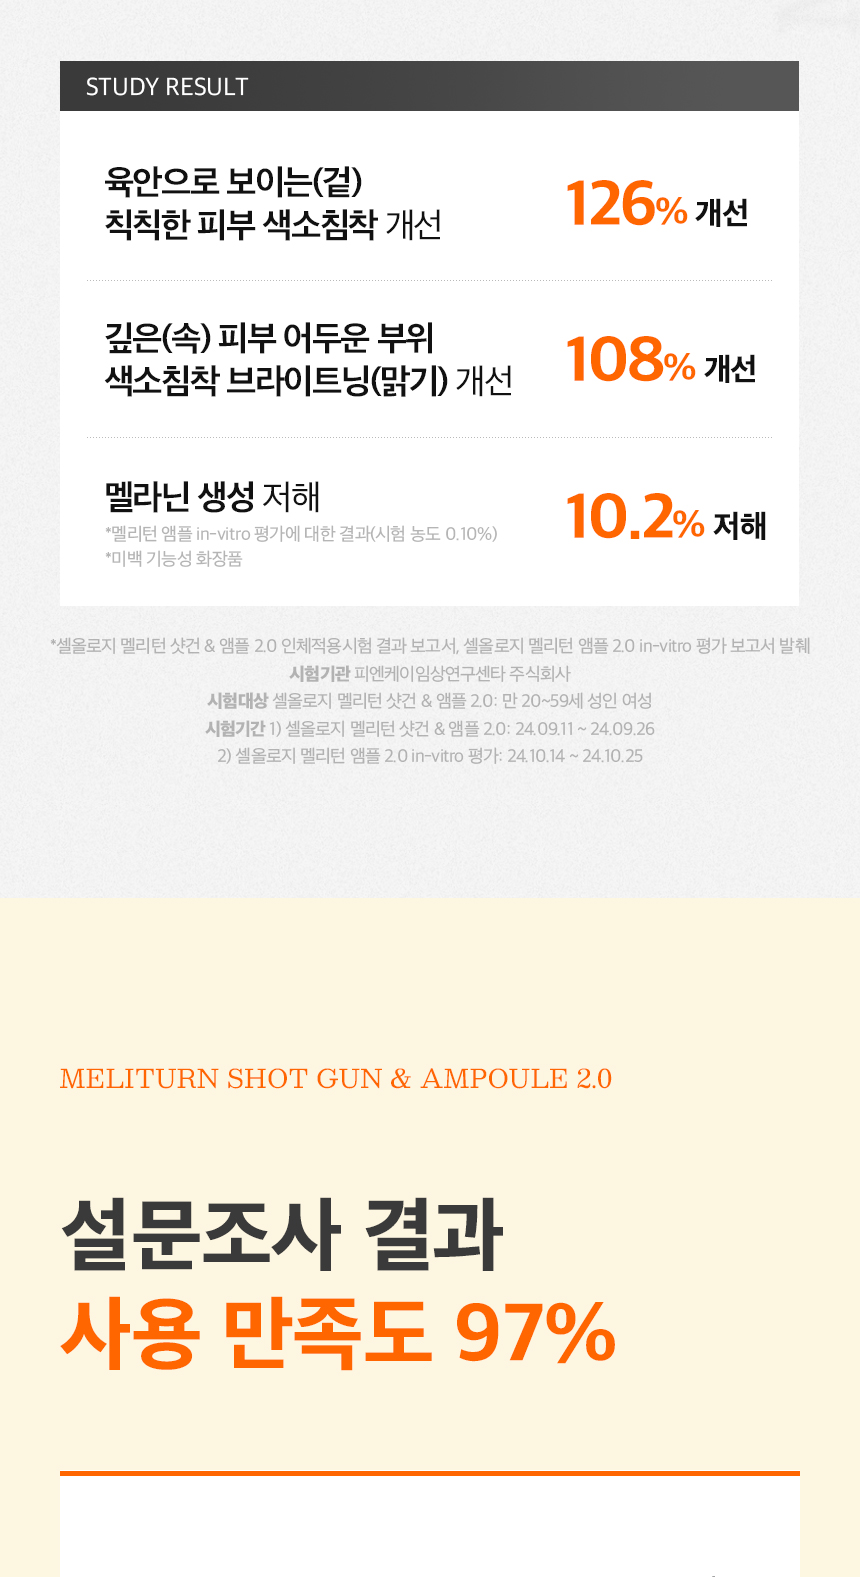

💡 Used in Korean skin clinics for visible brightening & tone-up results

✔️ LED + Micro-Vibration Shot Care – Pushes ampoule deep into the skin

✔️ Upgraded Brightening Ampoule 2.0 – Packed with Yuzu water, Niacinamide & Vitamin C

✔️ Targets dark spots, dullness & redness – Way more effective than a regular serum